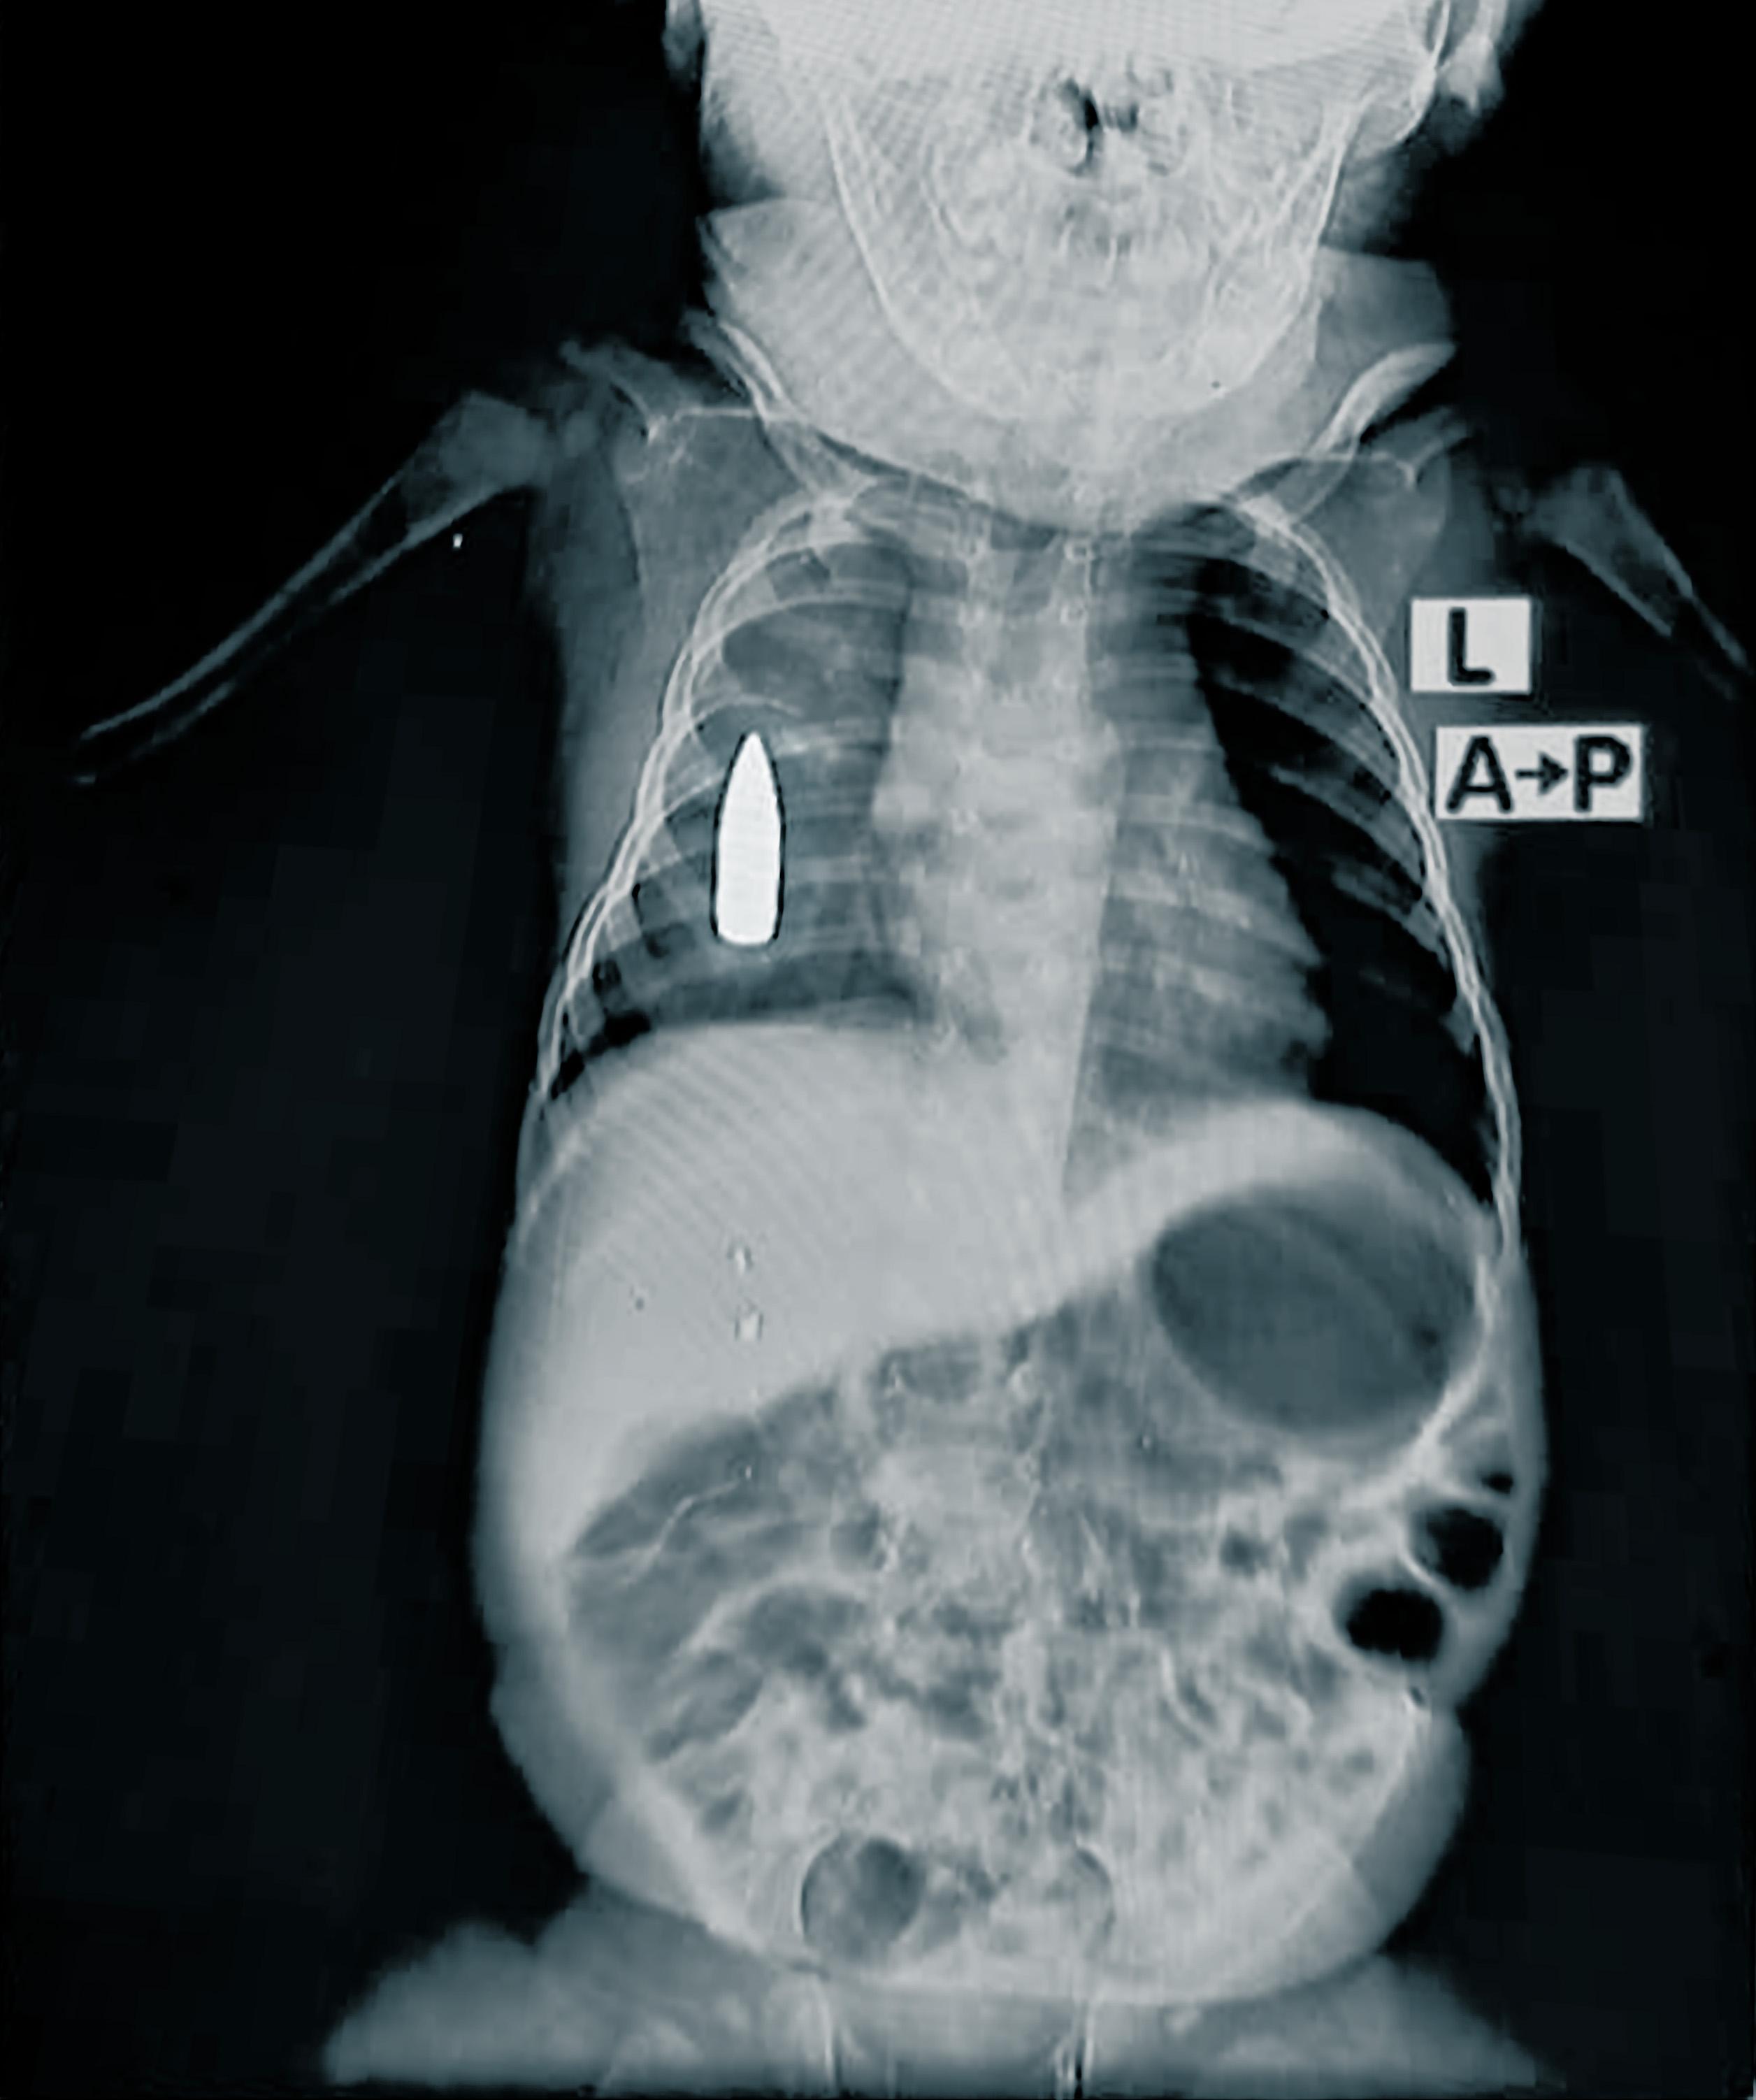

« Riyad, un bébé de 18 mois, a été amené aux urgences après avoir été touché par une balle perdue au côté droit alors qu’il dormait dans la maison familiale », explique le Dr Moeen*, responsable de l’équipe médicale de MSF.

« L’équipe médicale a lutté pendant quatre heures pour le stabiliser. En raison de la perte de sang importante, ses chances de survie à l’opération étaient de 50 %. »

L’équipe a pu stopper l’hémorragie, mais la balle est restée logée dans sa poitrine. On ne sait pas encore combien de temps il faudra attendre avant que quelque chose ne soit fait pour cela. L’hôpital ne dispose pas de capacités chirurgicales avancées, en partie à cause d’un blocage systématique de l’envoi de fournitures chirurgicales depuis octobre 2023. L’orientation des patients hors de la zone est également très difficile car les voies de transport sont soit détruites, soit beaucoup trop dangereuses.

Riyad est l’un des 314 enfants soignés pour des blessures par balle et par explosion en 2024.